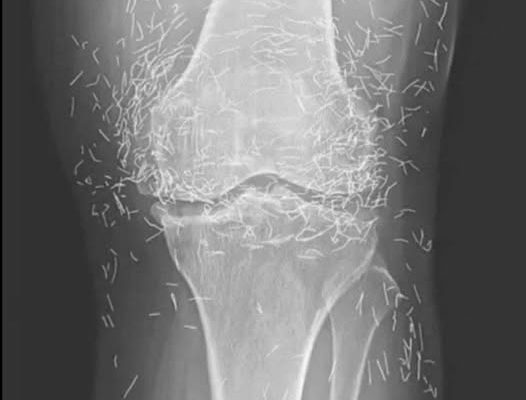

Years later, when doctors took X-rays to evaluate her knee condition, they weren’t prepared for what appeared on the images. Her knees were filled with dozens of bright, metallic flecks — tiny needles embedded deep within the joint area.

The findings were later documented in a case published by the New England Journal of Medicine.

Beyond inflammation, the needles created another problem: imaging complications. Metal objects can obscure parts of the anatomy on X-rays, making it harder for doctors to clearly assess joint damage or disease progression.

Even more concerning, the presence of metal inside the body can make certain scans dangerous. MRI machines rely on powerful magnetic fields, and embedded needles may shift during scanning, potentially damaging blood vessels or surrounding tissue. In short, future diagnostic options for this patient became limited.